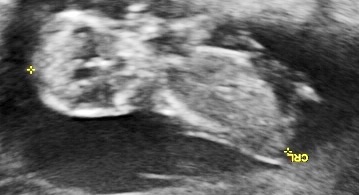

I was 11w5d when I had the scan, although I was measuring 12w1d. I know it's still pretty early, but am wondering if you see anything on these (terrible quality) scan pics! Attachment 23572Attachment 23571Attachment 23573Attachment 23574Attachment 23575